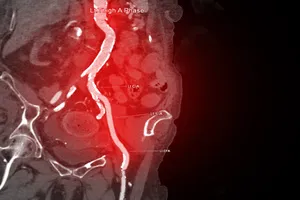

· 시술

7. 경피적 관상동맥 중재술 (PCI)

막힌 혈관 부위에 작은 절개를 하고 도관을 삽입하여 풍선으로 좁아진 부위를 넓히거나 스텐트를 삽입하여 혈관을 지지하는 시술입니다.